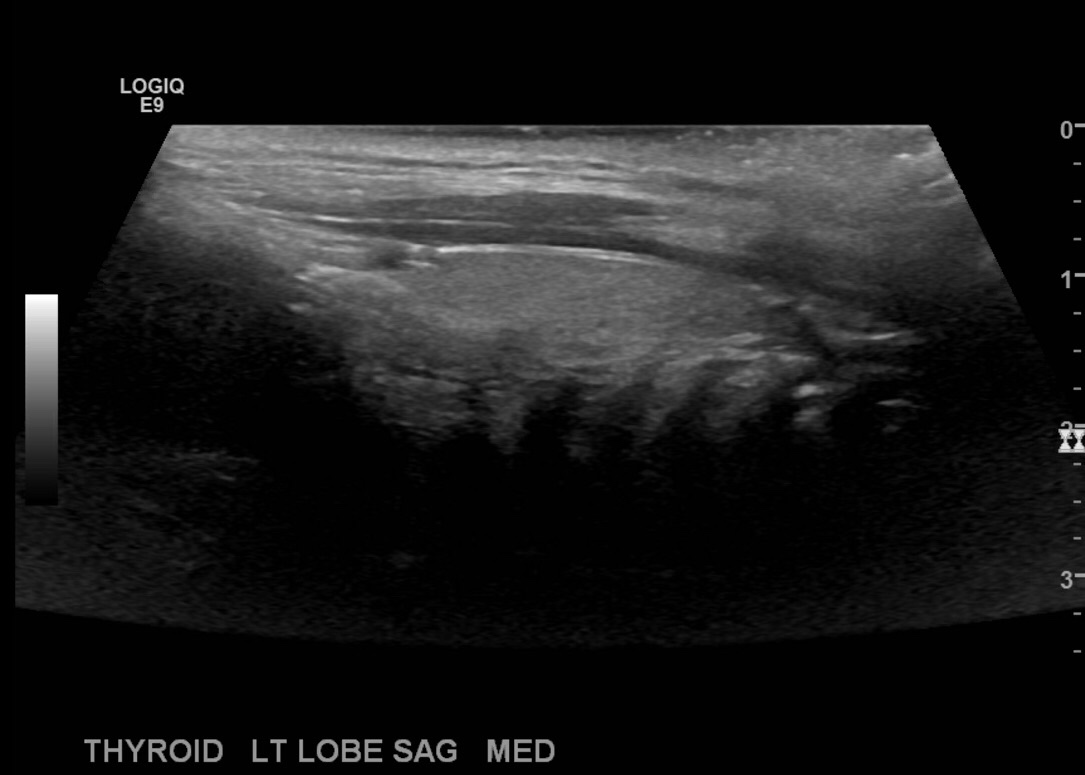

Repeat the process on the left.

Go to the right neck and take sagittal images in middle of the right thyroid lobe, lateral and medial.

Then measure the left thyroid lobe, length x width x height.